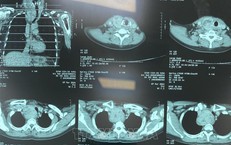

Cứu sống bệnh nhân vỡ động mạch chủ bụng bằng Stent graft

Y tế - 10/10/2025 14:54SKĐS - Vừa qua, các bác sĩ Bệnh viện Hữu Nghị đã cứu sống một bệnh nhân 76 tuổi bị vỡ túi phình kích thước gần 8cm (động mạch chủ) bằng kỹ thuật can thiệp nội mạch hiện đại, đây là một tình trạng cấp cứu y khoa có tỷ lệ tử vong cao.